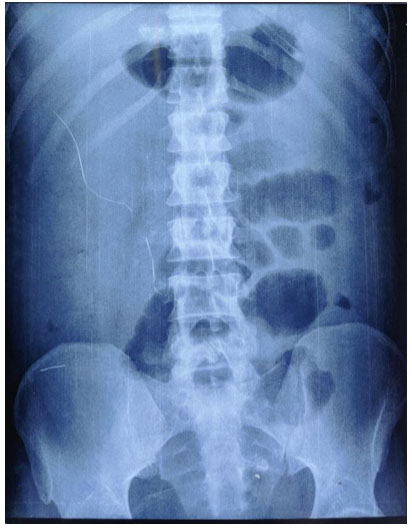

Two days later, he developed abdominal distension and on examination had guarding. Bowel sounds were sluggish. Repeat hemogram showed total leucocyte count of 30,000/mm3 with 88% polymorphonuclear cells. X-ray abdomen had no multiple air fluid levels (Figure 1 and Figure 2). Ultrasonography (USG) abdomen showed ascites and dilated bowel loops with loss of gut signature. Ascitic fluid showed more than 1000 cells/mm3 with 95% polymorphonuclear cells, sugar 119 mg, protein 2.81 g/dL, lactate dehydrogenase (LDH) 633 mg/dL, and serum ascites albumin gradient (SAAG) 0.46 suggestive of secondary bacterial peritonitis. Ascitic fluid culture was sent. Contrast-enhanced computed tomography (CECT) abdomen showed large bowel edema with small bowel dilatation suggestive of diffuse ischemic colitis (Figure 3).

Figure 1: X-ray abdomen left lateral position: No free air in abdomen.

Figure 2: X-ray abdomen erect position: No free air under diaphragm.